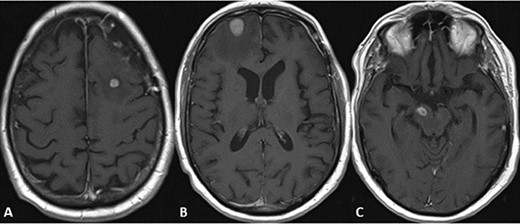

CASE

MRI scans indicating new metastatic lesions of the bilateral frontal lobes and right cerebral peduncle.